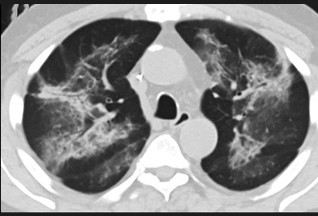

怎么“中度可疑”呢?这些专家表示,这5位患者的肺部CT都具备新冠肺炎CT的影像特征,比如肺部出现磨玻璃的影像,磨玻璃主要分布在双下肺靠近外周,出现铺路石征、严重的表现为双肺弥漫性多发实变。同时,其病程转归和临床特征也与新冠肺炎相似。

以下面这4张图涉及的这个美国“电子烟”病人为例,专家不是仅仅通过一张影片做判断的,而是通过这4张涵盖了这名病例肺部多天变化情况的影片进行的研判,认为该病例的病程进展跟新冠更为相似。